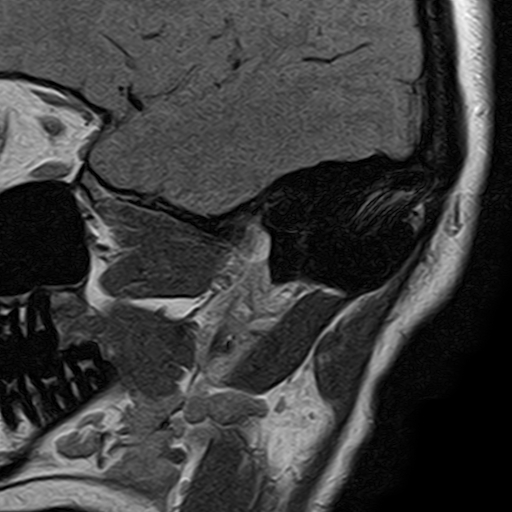

Пациент во время исследования находится внутри цилиндрической части томографа, лежа на выдвижном столе. Во время процедуры нужно сохранять неподвижность для получения качественных изображений исследуемой области.

Работа томографа сопровождается громким акустическим шумом, что обусловлено особенностями технологии процесса. Чтобы уменьшить дискомфорт от воздействия шума, можно надеть наушники или использовать беруши.

Пациентам, испытывающим тревогу и волнение, разрешается находиться в кабинете МРТ вместе с сопровождающим. Вызвать медработников из смежного помещения можно, воспользовавшись специальной сигнальной груши, которая в течение всего периода исследования находится в руке пациента.